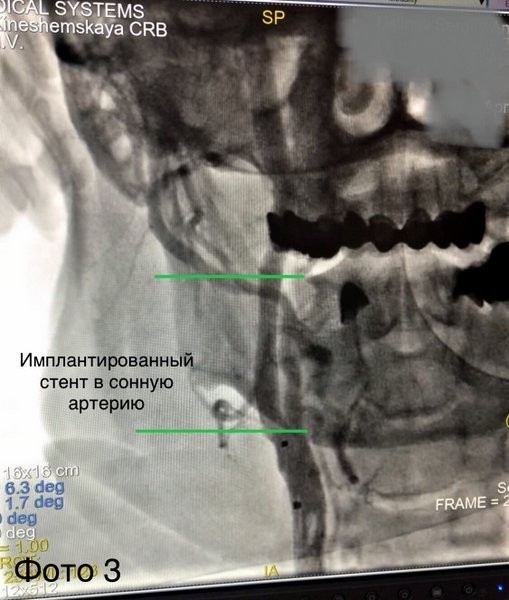

«Пациента взяли в операционную. По данным ангиографии в правой средней мозговой артерии визуализирован тромб (фото 1). Выполнили тромбоаспирацию (удаление тромба) из средней мозговой и стентирование сонной артерии (фото 3) с полным восстановлением кровотока по мозговым артериям (фото 4). Сразу после оперативного вмешательства пациент пришел в сознание. Далее наши специалисты: реаниматологи, неврологи, реабилитологи продолжили бороться за жизнь пациента. 16 дней командной работы позволили спасти его жизнь и восстановить работу мозга», — рассказал Михаил Лапин, заведующий отделением рентгенохирургических методов диагностики и лечения.